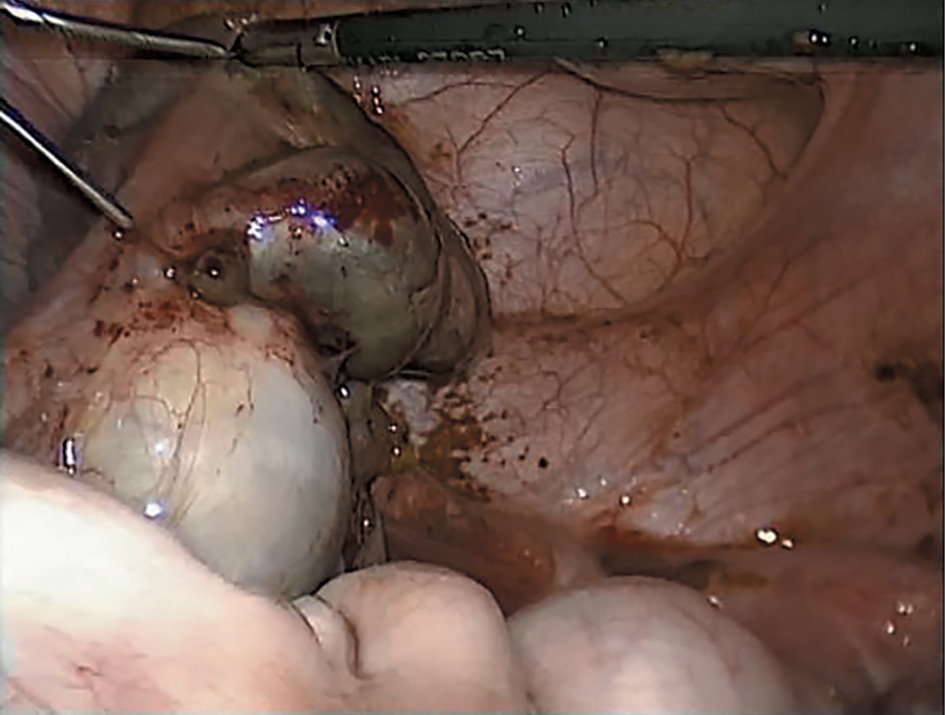

Во время лапароскопии визуализировано две матки однорогой формы. Левая – шаровидной формы, несколько увеличена в размерах. Левая маточная труба расширена, фимбриальный отдел не визуализируется, в спаечном конгломерате с яичником (рис. 2). В полость малого таза выступает образование 5,0×4,5 см – гематокольпос.

Рис. 2. Лапароскопическая картина конгломерата, представленного расширенной маточной трубой с запаянным ампулярным отделом и яичником слева.

Fig. 2. Laparoscopy of the conglomerate which is represented by a dilated fallopian tube with a sealed ampullary section and an ovary on the left.